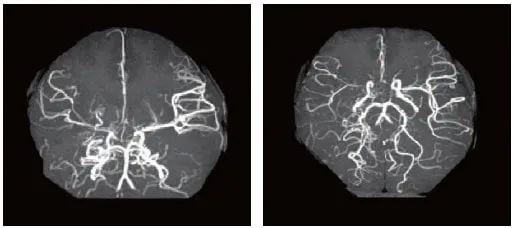

두개 내 양측 내경동맥 말단부위나 주요 가지 동맥의 점차적인 폐쇄로 특징적인 소견을 통해 진단합니다. 뇌 혈관 조영술에서 연기 같은 미세한 혈관들이 관찰되면 모야모야병으로 진단됩니다. 뇌혈역학적 검사(SPECT)를 통해 혈역학적 스트레스 정도를 평가하고 치료 방침을 결정합니다.

직접 혈관 문합술: 뇌 표면의 중대뇌동맥과 두피의 천측두동맥을 직접 연결하여 혈류량을 즉시 늘리는 방법입니다. 성인의 경우 효과적입니다.

간접 혈관 문합술: 두피, 근육, 경막 등의 혈관이나 혈관이 풍부한 조직을 뇌 표면에 얹어 신생혈관이 뇌 안으로 자랄 수 있도록 유도하는 방법입니다. 소아 환자에서 좋은 성적을 거두며 위험성이 적습니다. 2-3주가 지나면 뇌혈류가 증가됩니다.

복합 뇌혈관문합술: 직접 혈관 문합술과 간접 혈관 문합술을 병합하여 시행하는 방법으로, 성인에서는 간접문합술만으로 충분한 효과를 볼 수 없어 두 방법을 함께 시행합니다.

장기 관리

수술 후 최소 4~5년간 병원에 다니면서 치료를 받고 정기적으로 뇌혈류에 대한 평가를 시행해야 합니다. 시간이 지나면서 연결한 혈관이 굵어지고 혈류가 보강되어 뇌경색이나 뇌출혈을 예방합니다.